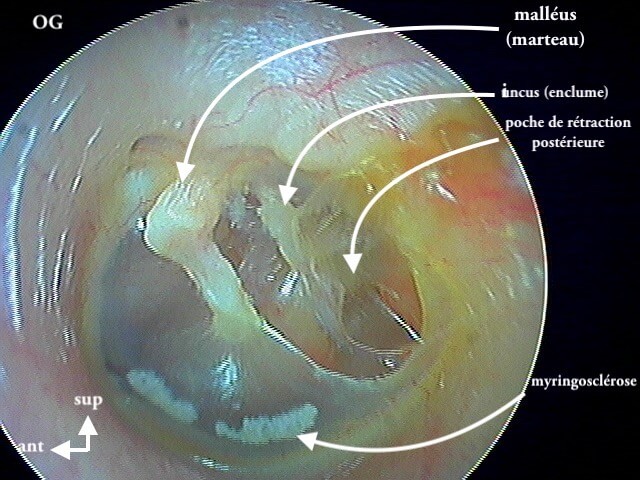

7 MYRINGOSCLÉROSE (ou TYMPANOSCLÉROSE)

Surcharge calcaire de la couche conjonctive tympanique: AUCUNE conséquence anatomique ou fonctionnelle (auditive), gêne parfois en cas de tympanoplastie. On parle plus de tympanosclérose quand ces plaques de calcaires (issues d'infections antérieures cicatrisées) sont dans la caisse; et de myringosclérose quand elles ne touchent que le tympan. En les voyant cela vous permettra d'affirmer que le patient·e a eu des otites dans l'enfance et puis c'est tout! Ces plaques sont superficielles et le tympan est normal, à ne pas confondre avec un cholestéatome.

8 POCHE DE RÉTRACTION (ou ATÉLÉCTASIE)

C'est volontiers dans mon expérience la pathologie la plus importante et la plus difficile du diagnostic otoscopique pur. On bascule entre la surveillance clinique annuelle (abstention thérapeutique) et l'interventionnisme chirurgical pour éviter le cholestéatome (qui parfois est iatrogène pour l'audition résiduelle).

J'utilise plus le terme de poche de rétraction plutôt qu'otite atéléctasique.

Donc il faut caractériser ces poches de rétraction (+/- associée à myringosclérose, perforation tympanique, OSM) par:

1/autonettoyante: non cholestéatome

2/ mobilisable au Valsalva: pas d'aérateur (juste surveillance annuelle)

3/ contrôlable à l ’optique: pas de tympanoplastie (DANGER si on ne voit pas le bout de la poche qui s'invagine: risque de cholestéatome)

4/ localisation: pars flaccida (rétraction atticale ou épitympanique) ou pars tensa (rétraction atriale ou mésotympanique)